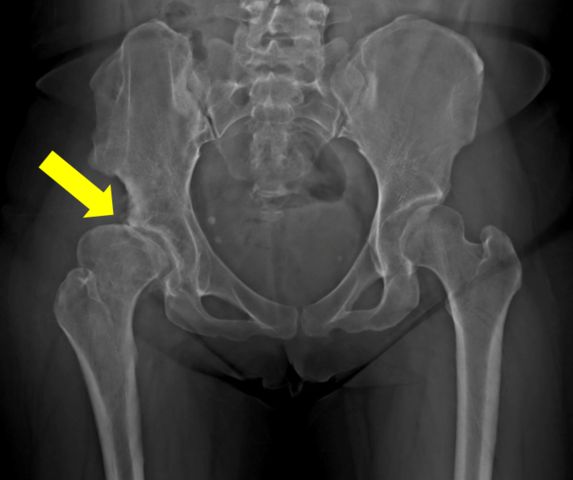

黃贊文醫師指出,髖關節發育不良導致的髖關節炎好發在40至55歲,女性居多。在髖關節炎初期可進行髖關節截骨矯正手術來延緩置換人工關節的時間;但若已進展到末期,治療的方式則是直接安排人工髖關節置換手術。